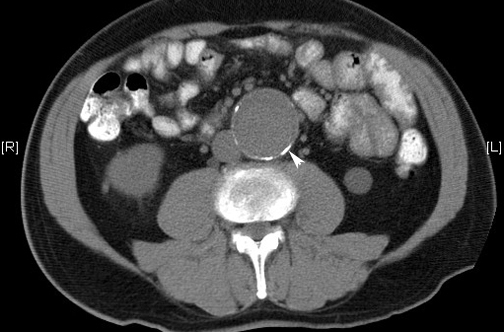

CT: Abdominal Aortic AneurysmCalcification of wall of the aortic aneurysm. |